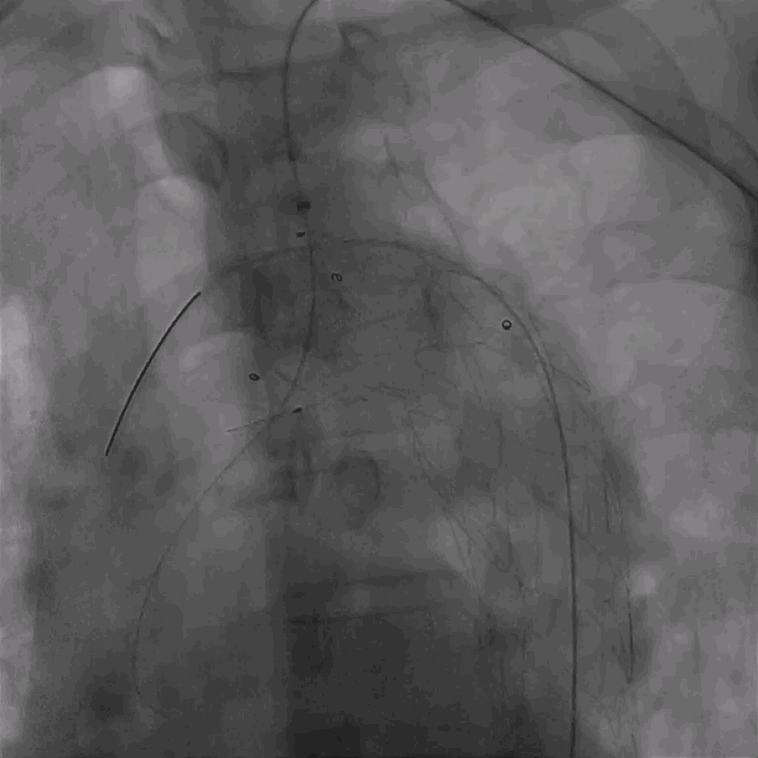

02. 交换0.035"Lunderquist超硬导丝至升主动脉,于左侧颈总动脉开口远端精确定位并释放华脉泰科PTBS3632180覆膜支架。

泥鳅导丝怎么用曲乐丰教授团队:0.018"和0.035"普通泥鳅导丝行胸主动脉弓上分支原位开窗的病例分享_https://www.jmylbn.com_新闻资讯_第28张

植入华脉泰科覆膜支架

泥鳅导丝怎么用曲乐丰教授团队:0.018"和0.035"普通泥鳅导丝行胸主动脉弓上分支原位开窗的病例分享_https://www.jmylbn.com_新闻资讯_第29张

释放华脉泰科支架前三节,再次造影确认位置

泥鳅导丝怎么用曲乐丰教授团队:0.018"和0.035"普通泥鳅导丝行胸主动脉弓上分支原位开窗的病例分享_https://www.jmylbn.com_新闻资讯_第30张

全部释放并造影确认支架形态